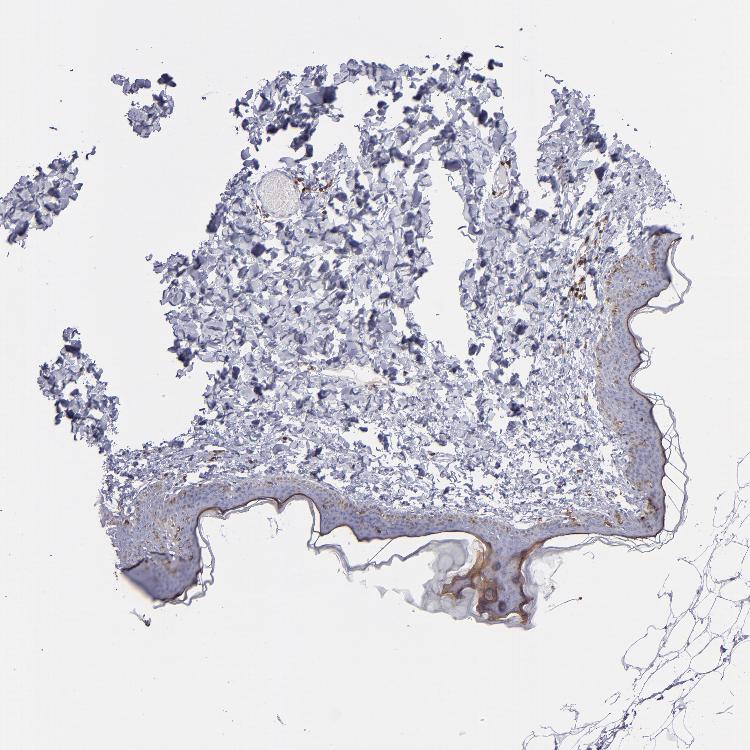

SKIN 1 - Antibody stainingi

Antibody staining in the annotated cell types in the current human tissue is reported as not detected, low, medium, or high, based on conventional immunohistochemistry profiling in selected tissues. This score is based on the combination of the staining intensity and fraction of stained cells.

Each image is clickable and will lead to virtual microscopy that enables deeper exploration of all samples and also displays staining intensity scores, fraction scores and subcellular localization as well as patient and tissue information for each sample.

Antibody CAB002498

Cells in basal layer Not detected

Cells in corneal layer Not detected

Cells in granular layer Medium

Cells in spinous layer Not detected

Endothelial cells Not detected

Extracellular matrix Not detected

Fibrohistiocytic cells High

Langerhans cells Medium

Lymphocytes Not detected

Melanocytes Not detected

Vascular mural cells Not detected